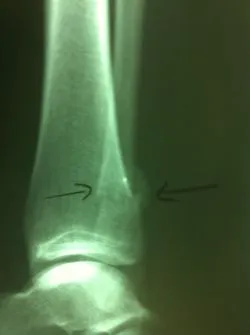

Stress fractures are often a clinical diagnosis as x-rays may be negative initially. The patient would typically experience pain and swelling across the top of the metatarsals. The pain would be mild in the morning. However, would get worse with weight-bearing. When x-rays are negative these problems are still treated as a fracture. X-rays taken 14-21 days after the injury will often show healing of the stress fracture by bone callus along the shaft of the bone.

Stress fractures that occur towards the end of the bone in the metaphyseal region often go nondisplaced after the healing process.

Stress fractures that occur in the midportion of the metatarsal can displace up, causing the potential for future problems in the metatarsal head region.